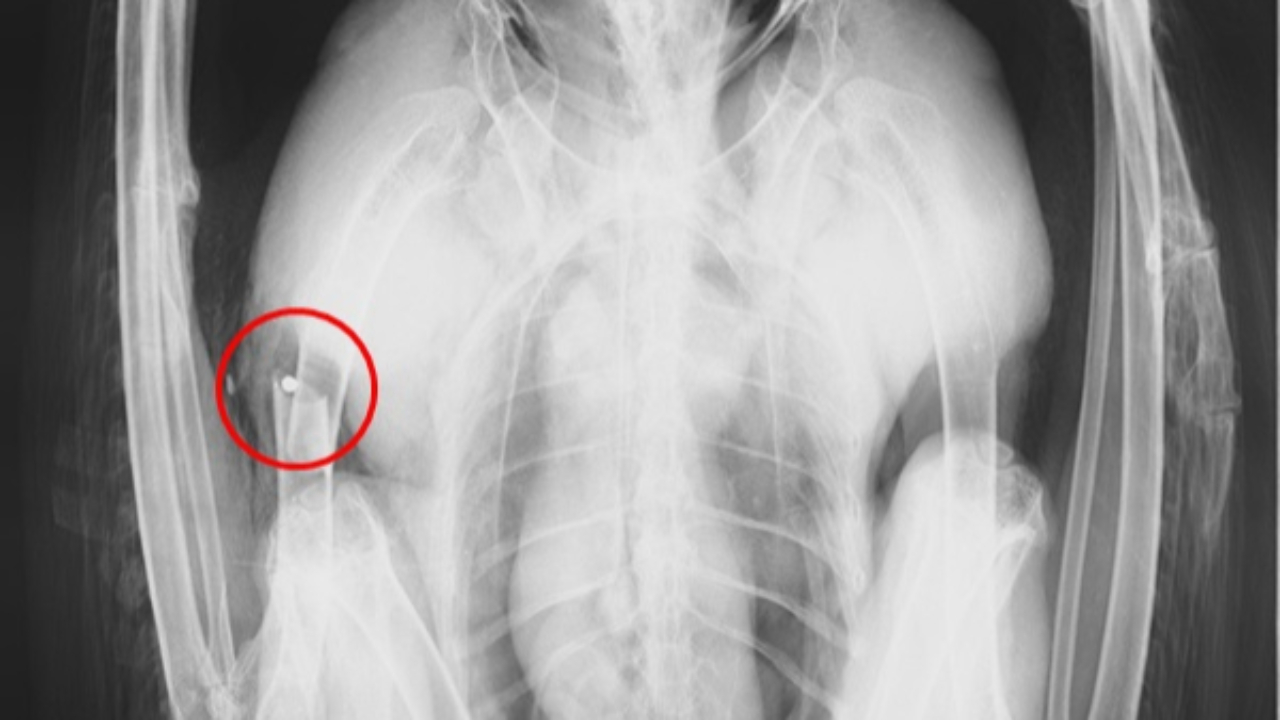

L'oiseau majestueux, retrouvé sur la commune de Saint-Michel-de-Saint-Geoirs, avait été victime d'un tir d'arme à feu. Il a reçu au moins un plomb, entraînant une fracture ouverte de l'humérus droit. Dans sa chute, l'aigle a subi un violent choc frontal au niveau du crâne, provoquant des dégâts oculaires.